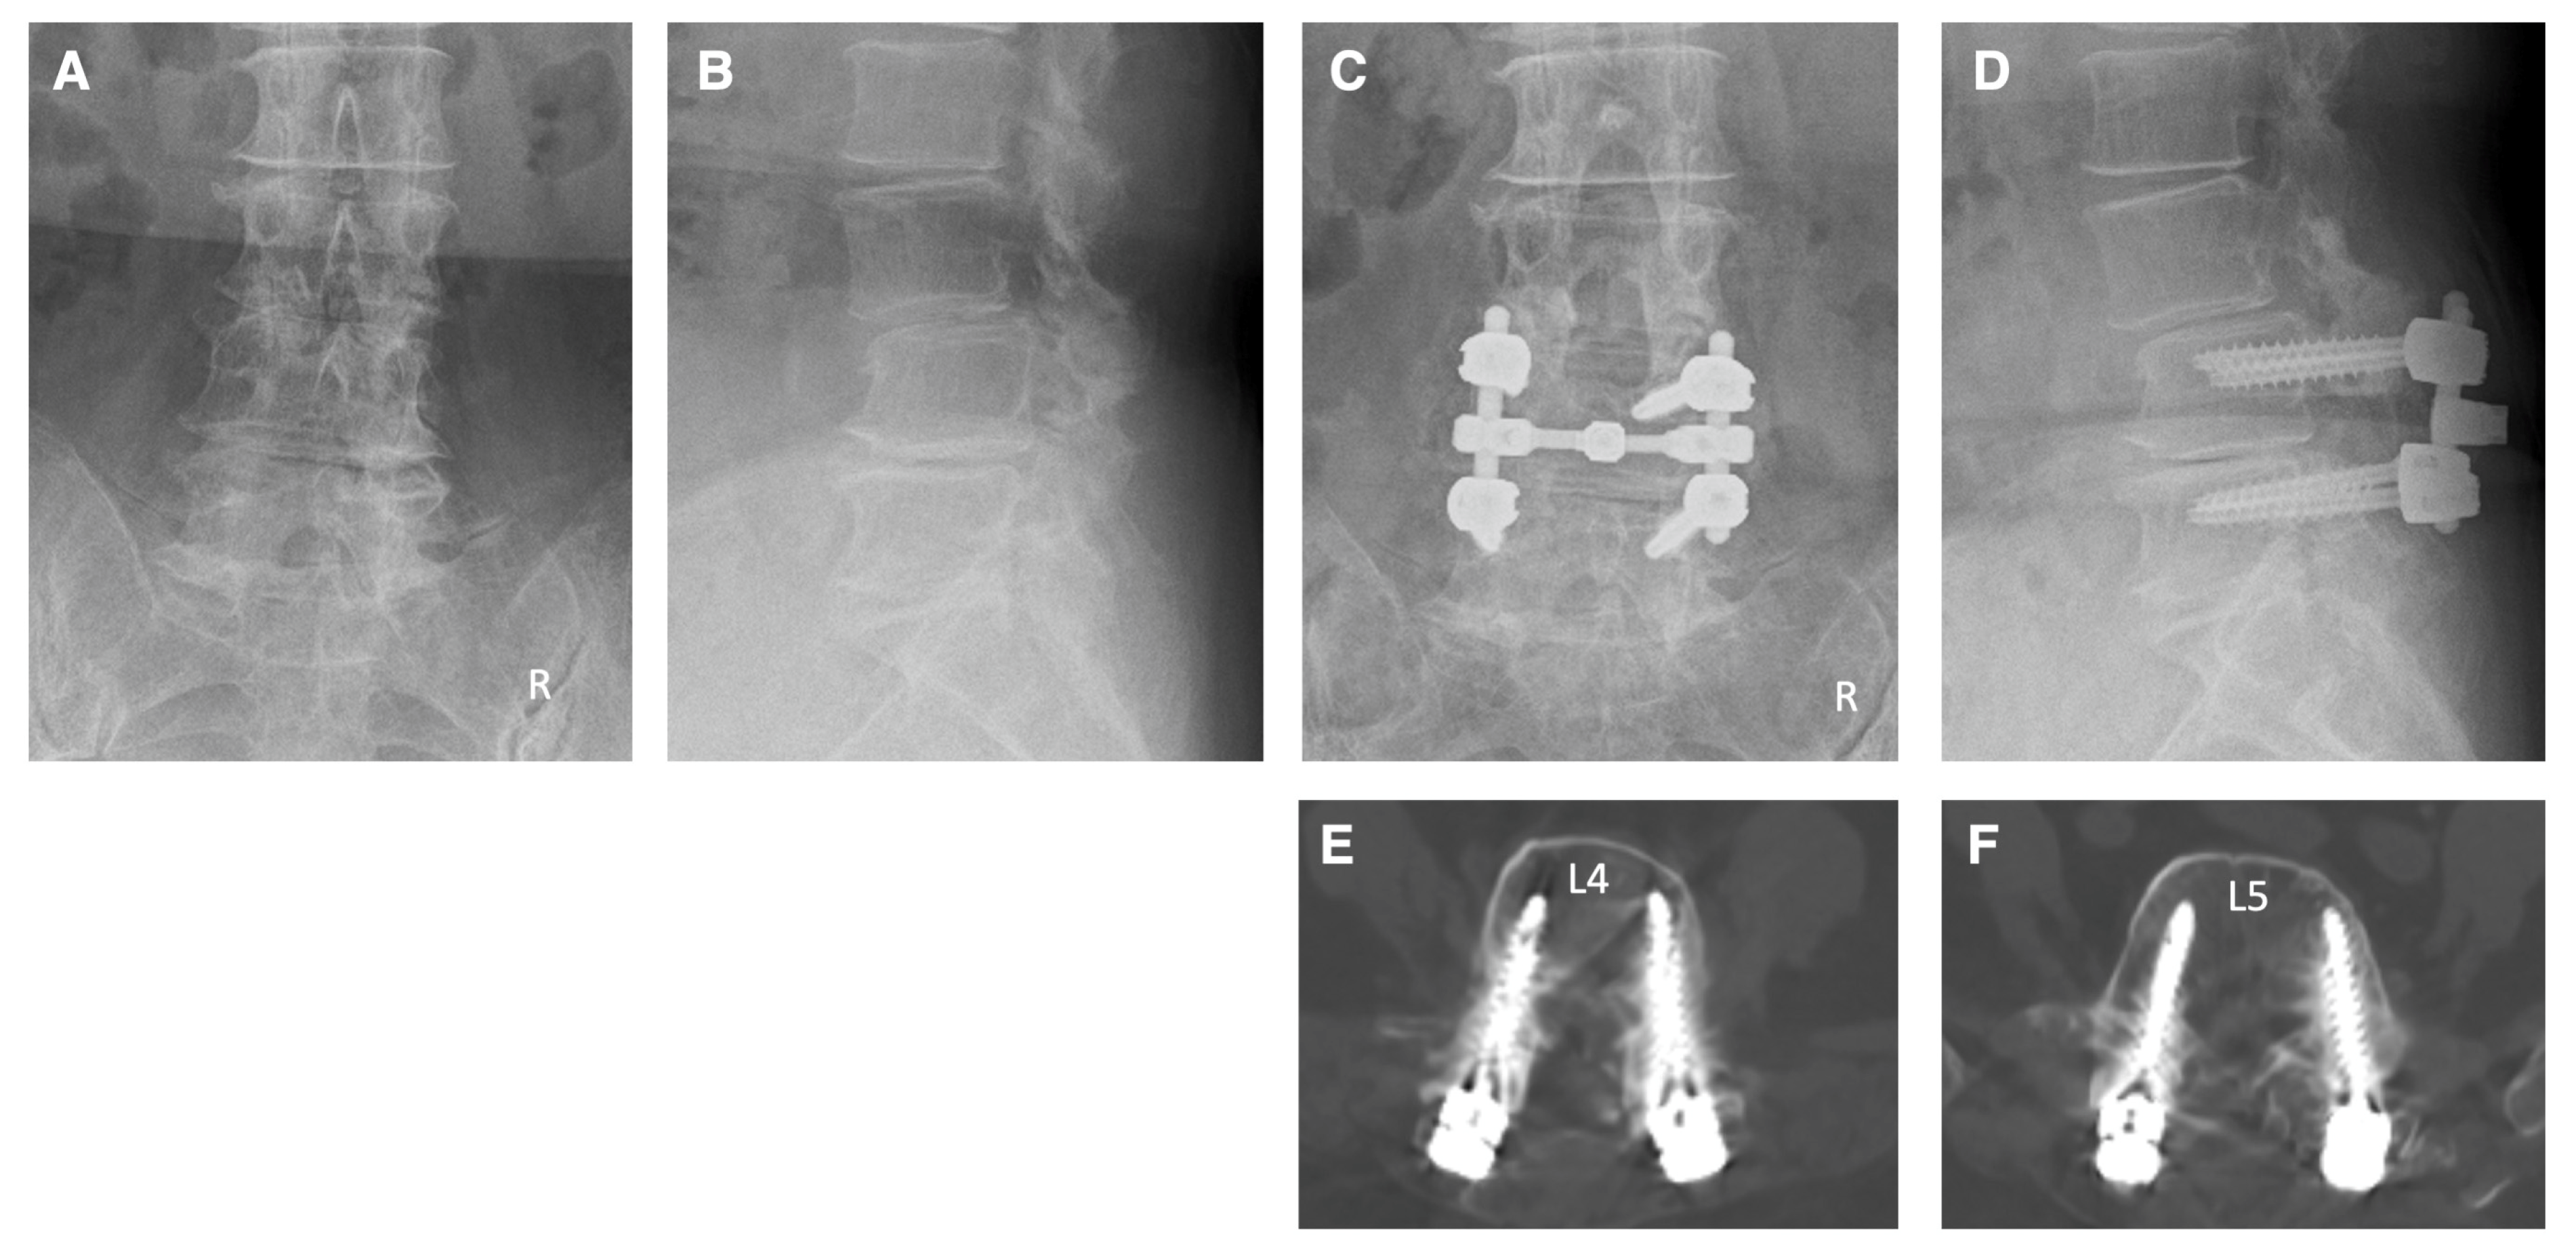

4. Illustrative Cases